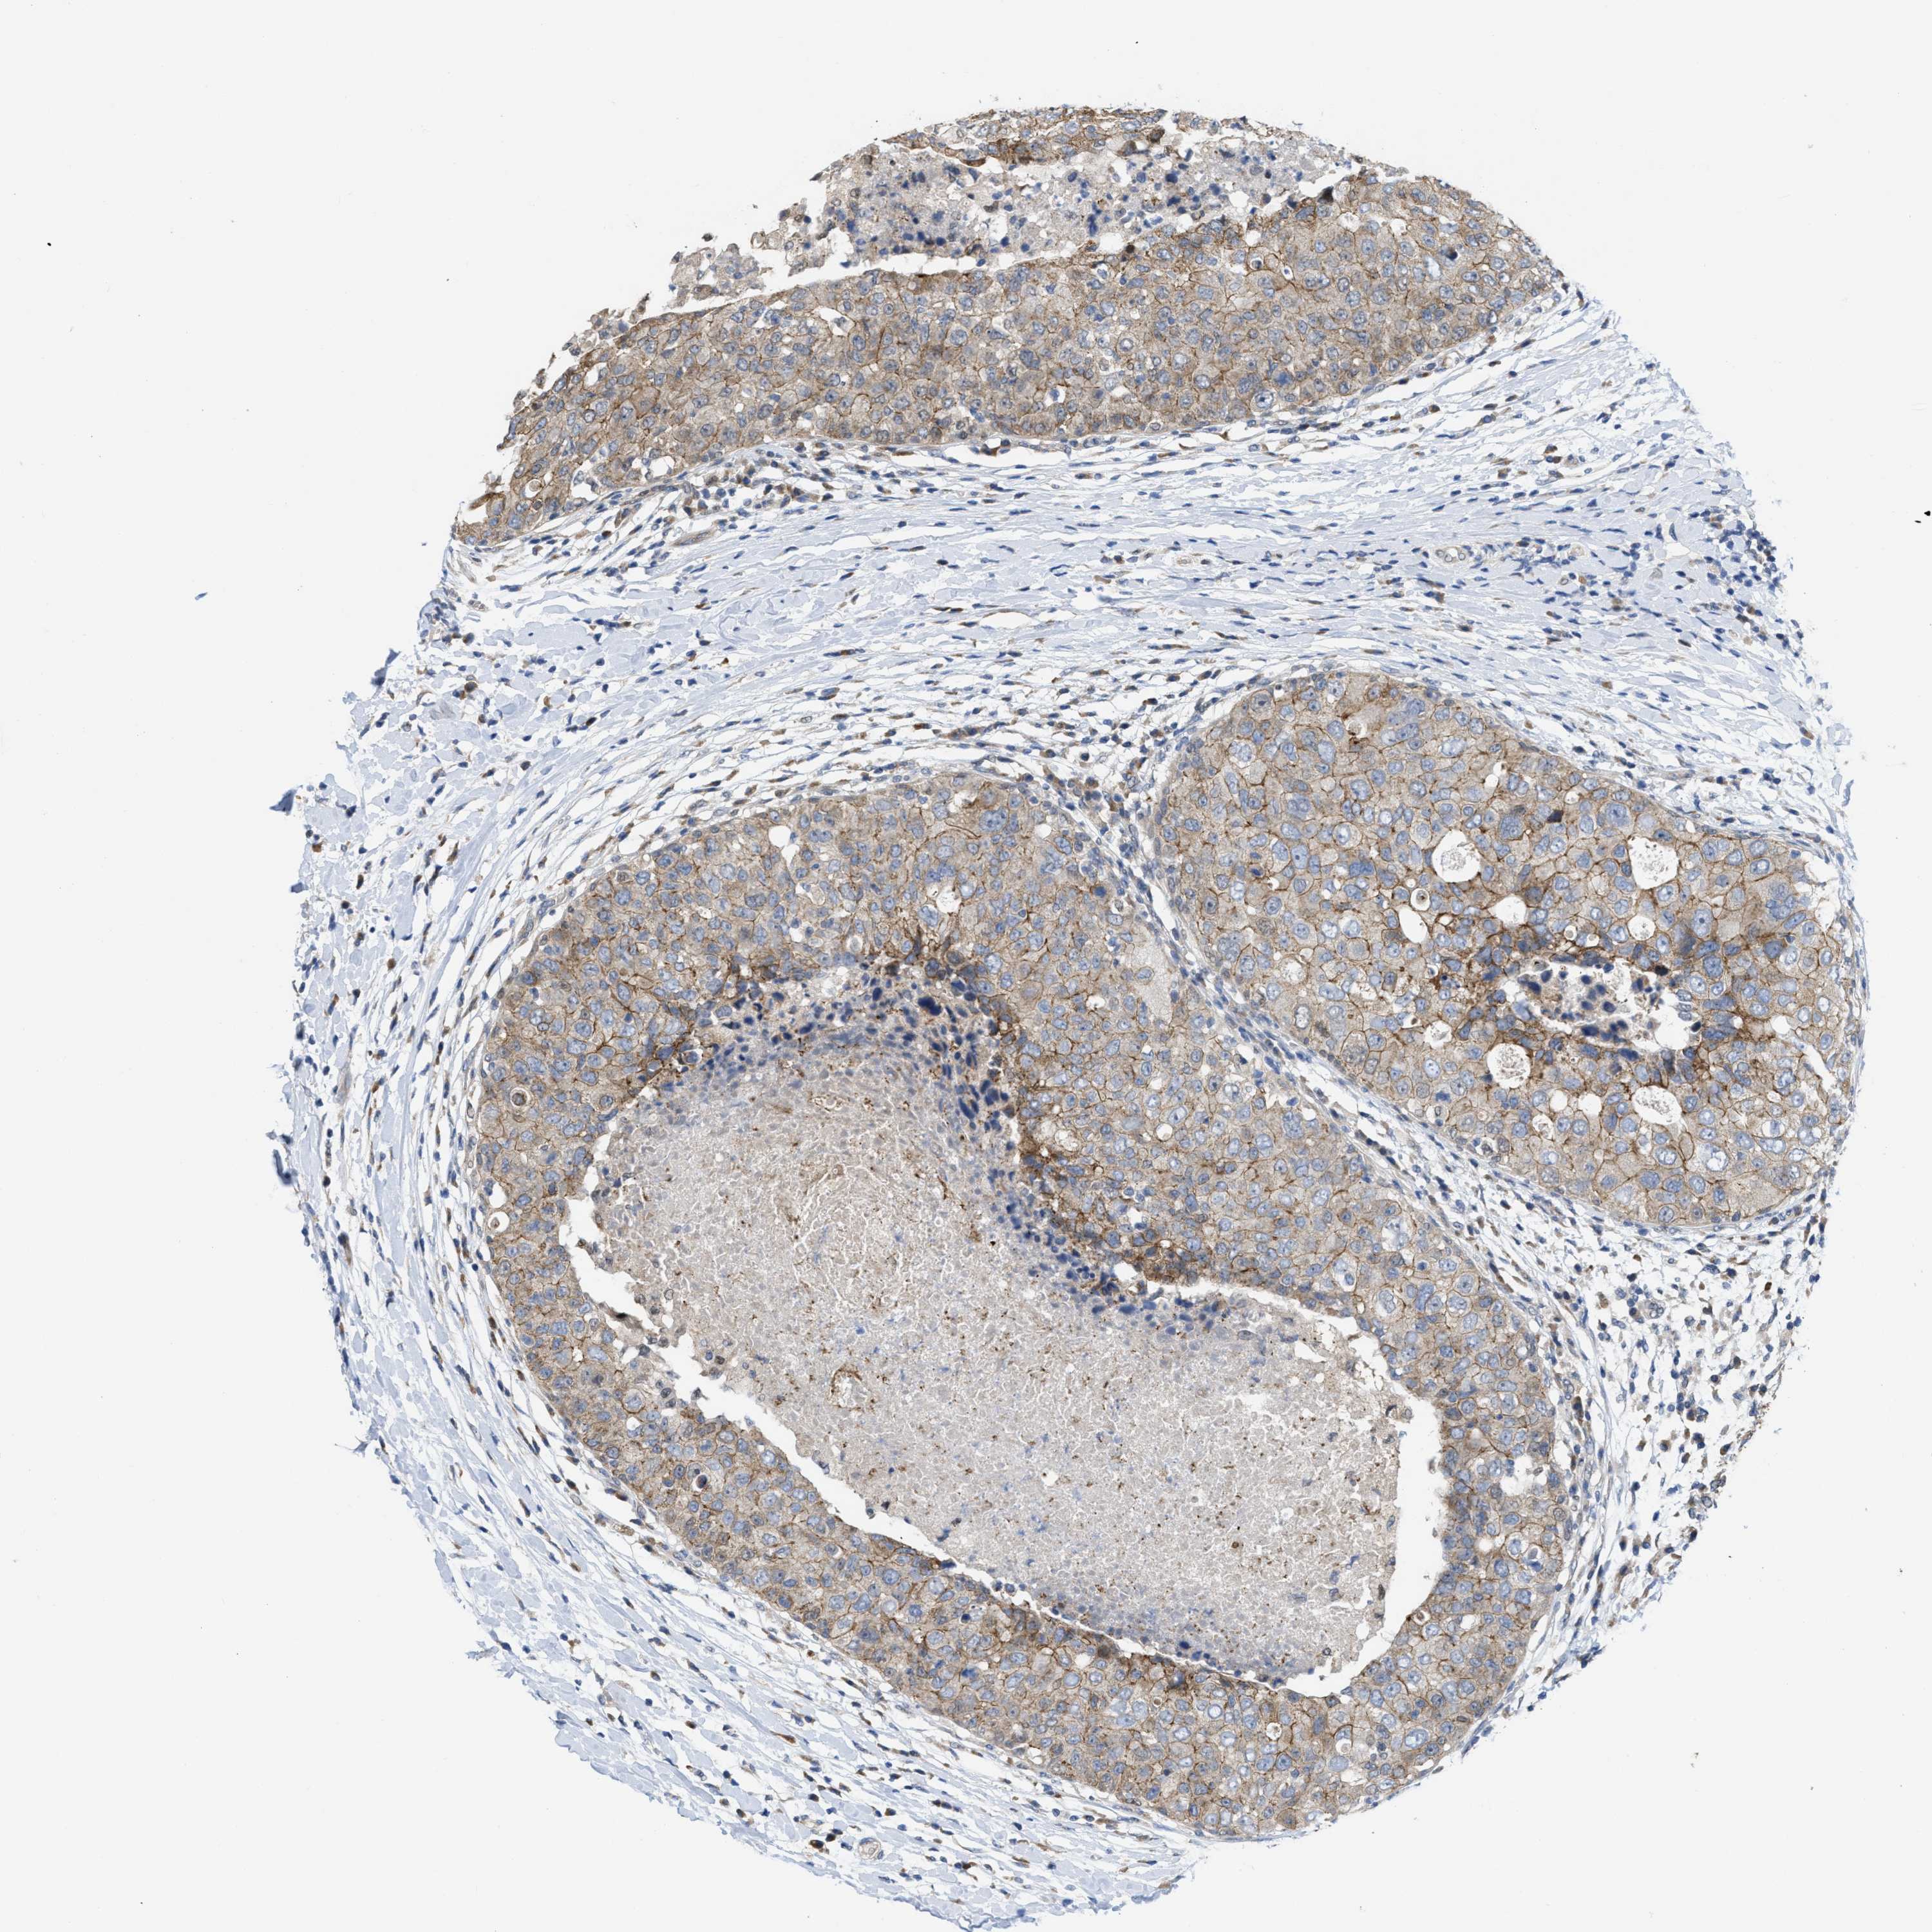

CANCER BREAST CANCER Show tissue menu

BRCA TCGA BRCA VALIDATION PROTEIN EXPRESSION